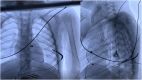

We present a case of successful implantation of a cardioverter-defibrillator (ICD) using combined technique in a child with Timothy's syndrome. Due to high risk of sudden cardiac death (SCD) such patients often need ICD for primary or secondary prevention but implantation technique in young children remains controversial. The subcutaneous cardioverter-defibrillators could be an option in some cases, however, reliable cardiac pacing should be implemented for patients with bradyarrhythmias. An ICD implantation technique with the epicardial pacing lead placement and subcutaneous tunnel formation for endocardial defibrillation lead seems to be promising in SCD prevention also providing the opportunity for permanent pacing.